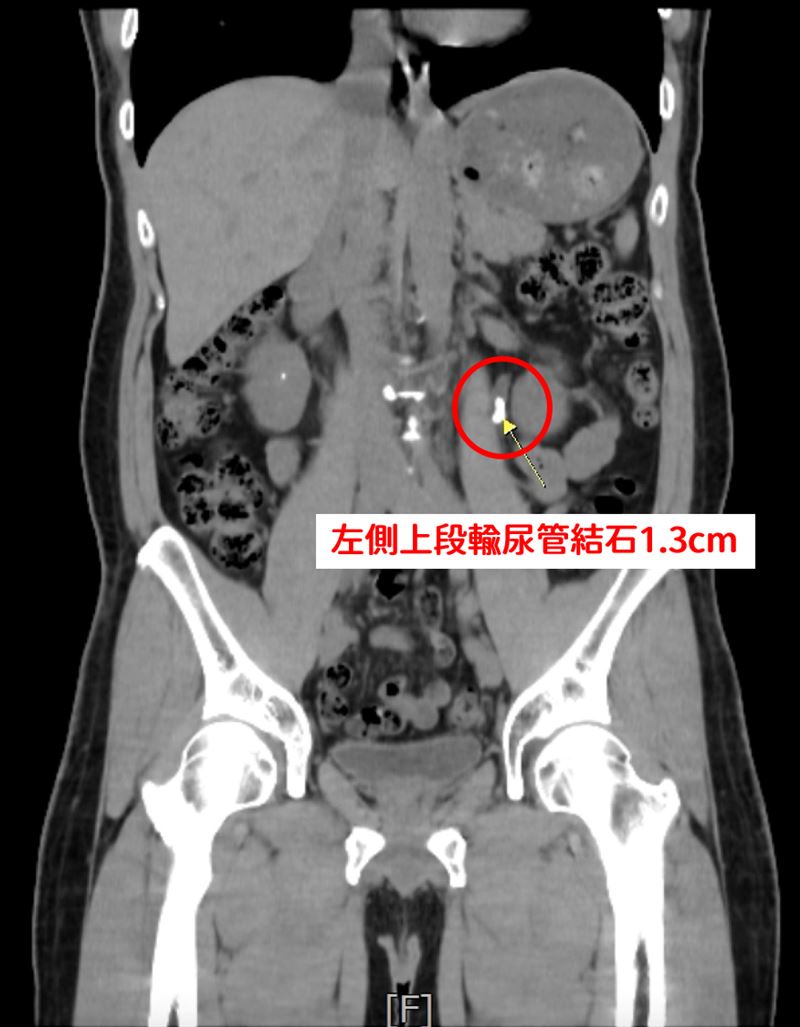

一名45歲男性,因血尿及左側腰部疼痛持續數週就醫,求診中國醫藥大學新竹附設醫院,先經X光檢查,發現患者左側腎盂輸尿管交接處約有1.3公分結石,合併左腎多顆小結石。初期接受兩次體外震波碎石術治療,但門診追蹤顯示結石未明顯改善,經醫病溝通後,改採軟式輸尿管鏡逆行性腎臟內取石手術,處理約36顆結石,手術約2小時,術後隔天即可出院,病患不再疼痛,半年門診追蹤即可。

王曦賢指出,該個案術前進一步安排電腦斷層檢查時,意外發現患者右側腎臟與輸尿管亦有細小結石。不宜腎臟兩側執行體外震波碎石術,未來可能造成結石雙側阻塞,嚴重時恐導致腎功能受損,甚至需緊急洗腎。因此在與患者充分溝通後,決定進行軟式輸尿管鏡逆行性腎臟內取石手術,一次解決雙側結石問題,降低風險。該患者一次手術後,處理約36個腎結石。